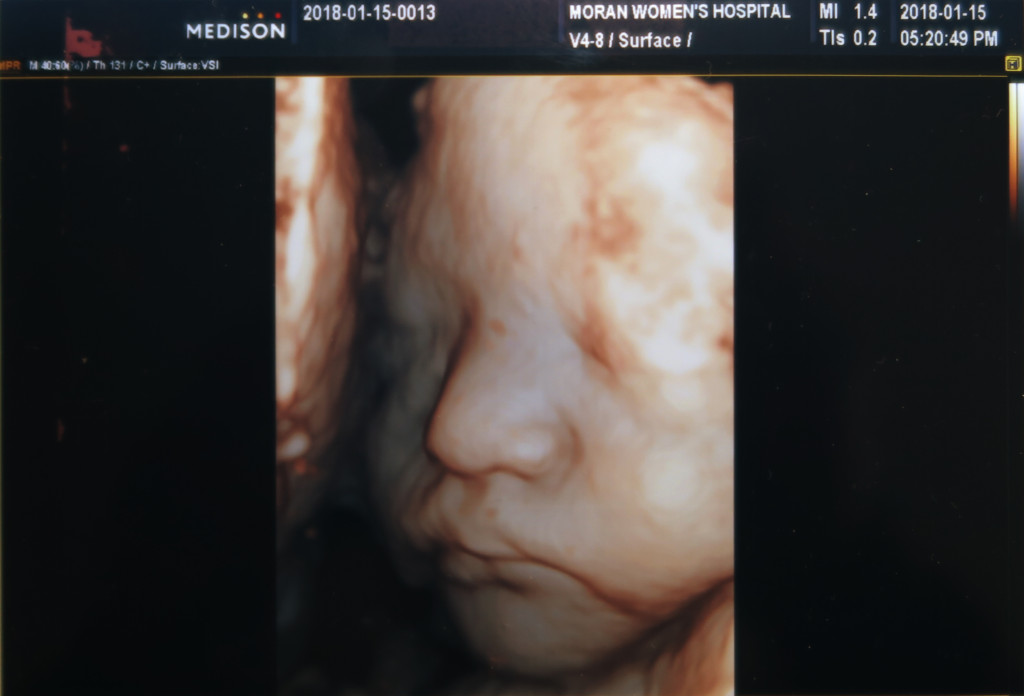

이사진은 잠자는 랑구 표정 판박이네요 ㅋㅋ

서현이 때는 아빠가 한번도 초음파 검사 하는걸 놓친적이 없는데.

이날은 서현이가 차에서 잠드는 바람에 아빠는 차에서 서현이 깨는거 기다린다고 사진만 보게 되었어요 ㅎㅎ

가운데 있는게 코고, 밑에 콧구멍 두개가 보입니다^^